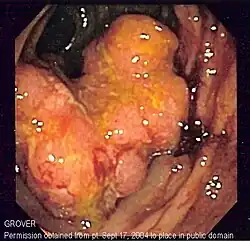

Macroscopie

C'est une tumeur le plus souvent ulcérée à sa partie centrale, avec un bourgeonnement plus ou moins marqué en périphérie et une infiltration pariétale qui s'étend vers la séreuse ; elle est rarement végétante (cæcum). Elle occupe une partie ou la totalité de la circonférence colique[réf. nécessaire].

Apparence de l'intérieur d'un côlon développant un carcinome colorectal invasif (tumeur de forme irrégulière formant ici un cratère rougeâtre).